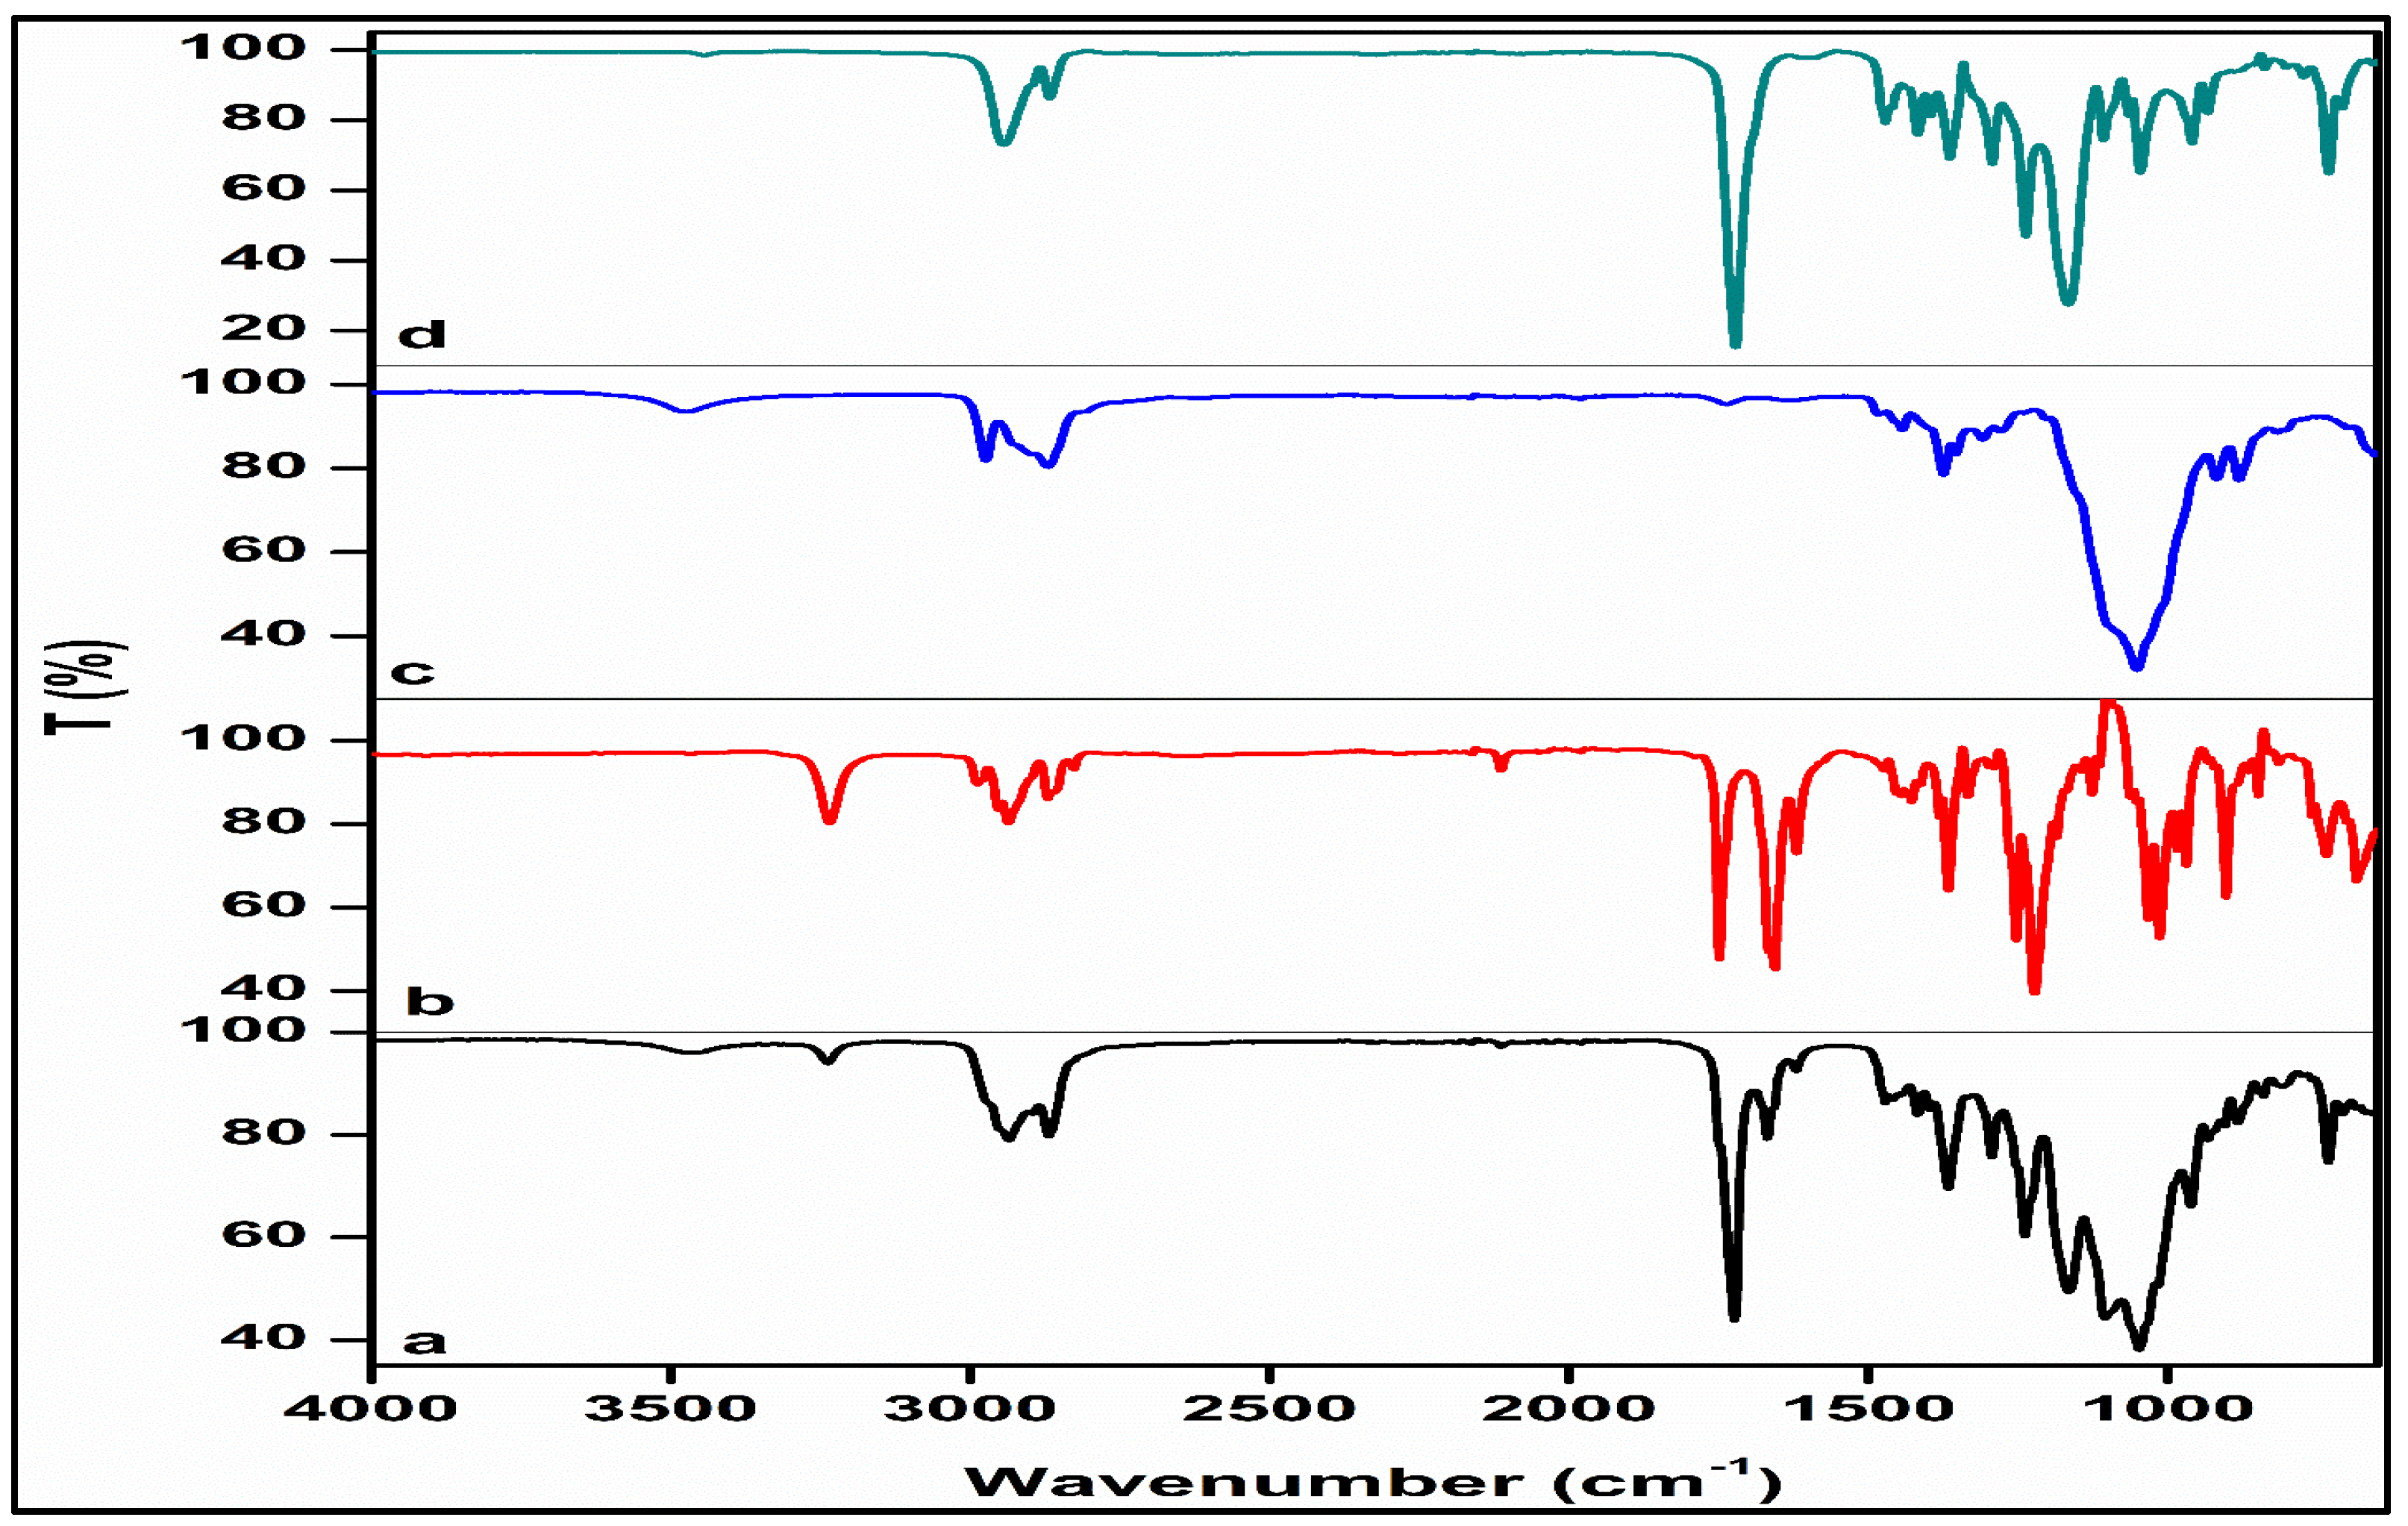

3.2.2. Structural Profiling

- Desai, J.; Alexander, K.; Riga, A. Characterization of polymeric dispersions of dimenhydrinate in ethyl cellulose for controlled release. Int. J. Pharm. 2006, 308, 115–123. [Google Scholar] [CrossRef] [PubMed]

- Abdelrazek, E.; Hezma, A.; El-Khodary, A.; Elzayat, A. Spectroscopic studies and thermal properties of PCL/PMMA biopolymer blend. Egypt. J. Basic Appl. Sci. 2016, 3, 10–15. [Google Scholar] [CrossRef]

- Javaid, S.; Ahmad, N.M.; Mahmood, A.; Nasir, H.; Iqbal, M.; Ahmad, N.; Irshad, S. Cefotaxime loaded polycaprolactone based polymeric nanoparticles with antifouling properties for in-vitro drug release applications. Polymers 2021, 13, 2180. [Google Scholar] [CrossRef]

- Horvat, G.; Žvab, K.; Knez, Ž.; Novak, Z. Simple, One-Pot Method for Preparing Transparent Ethyl Cellulose Films with Good Mechanical Properties. Polymers 2022, 14, 2399. [Google Scholar] [CrossRef]

- Phadke, K.V.; Manjeshwar, L.S.; Aminabhavi, T.M. Microspheres of gelatin and poly (ethylene glycol) coated with ethyl cellulose for controlled release of metronidazole. Ind. Eng. Chem. Res. 2014, 53, 6575–6584. [Google Scholar] [CrossRef]